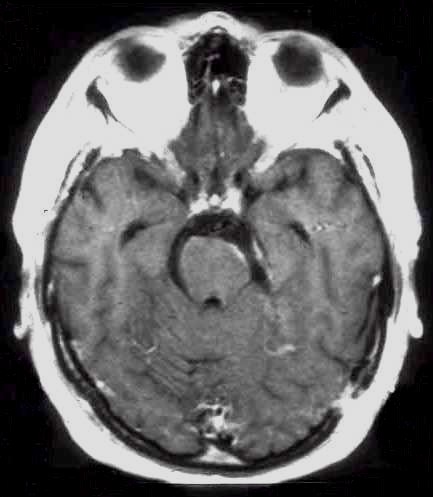

Voluminosa lesione in

sede crtca

Controllo RM

postoperatrio

Astrocitoma talamico

Indagine RM

postchirurgca

Rappresenta l'esempio migliore di un glioma ben circoscritto che può essere asportato anche da sedi particolarmente critiche dove pure la grandezza della lesione non pregiudica un'indicazione chirurgica. |